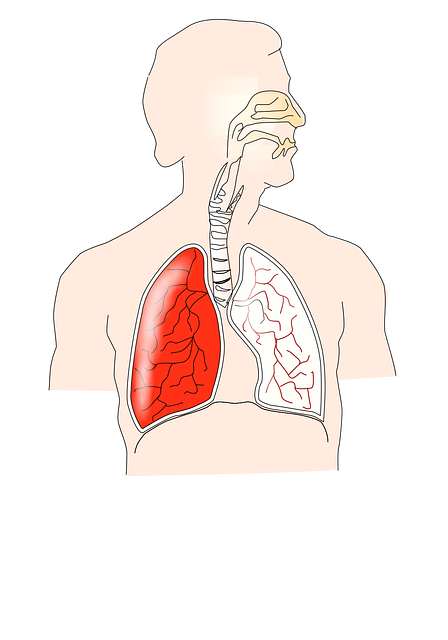

폐암의 경우 초기에는 증상이 없는 경우가 흔히 있으며 통증도 증상도 없이 생활하다가 건강검진을 통해 발견하는 경우도 생각보다 흔합니다. 폐암 증상은 기침 흉통 목소리의 변화 체중감소 호흡곤란 각혈 같은 증상을 보입니다. 오늘은 폐암 초기증에 대해서 알아보겠습니다.

폐암은 폐에 악성종양 암세포가 증식하여 덩어리를 형성해 폐기능의 문제가 생기게 하는 질환으로 진행이 심할 경우 다른 장기로 전이되기도 합니다. 진행 정도가 심하지 않은 경우 수술적 치료와 약물치료를 통해 증상을 완화할 수 있는 질병으로 알려져 있습니다. 폐암 초기에는 수술로 완치가 가능하며 예후도 좋은 편이지만 1~4기까지의 진행 정도에 따라서 사망률이 높아지는 질환입니다.

5. 호흡곤란

폐암이 생긴 경우 암덩어리가 점차 커지면서 호흡곤란을 유발하게 됩니다.